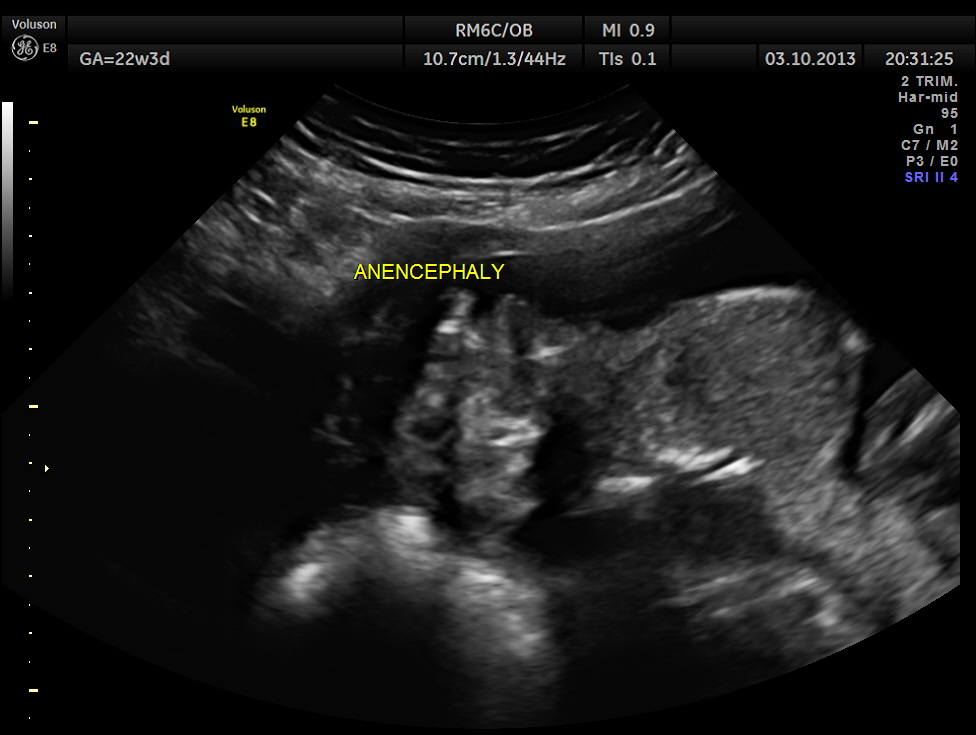

This was 20 year old primi , who was sent for routine anomaly scan around 22 weeks of gestation. There was no history of consanguinity. She had undergone 2 scans earlier , one at 7 weeks and another at 9 weeks. In between ,according to the patient she was not advised scan when she went for her ante natal clinical check ups.

The scan revealed anencephaly , which would have been picked up , if a scan had been done any time after 12 weeks of gestation. That was a depressing thought.

This fetus had anencephaly , horse shoe kidneys and abnormal appearance of spine .